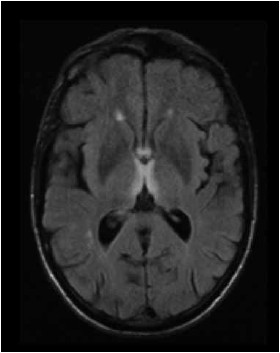

Paciente do sexo masculino, 12 anos, com quadro de diplopia, vertigem e dificuldade de marcha há 1 semana e, há 1 dia, evoluiu com sonolência. Tem diagnóstico de carcinoma de nasofaringe e perda de peso grave nos últimos meses. Ao exame físico, apresenta oftalmoparesia global e ataxia. Realizou o exame de imagem conforme mostrado a seguir. O líquor é normal.

O tratamento desse paciente deve ser realizado com